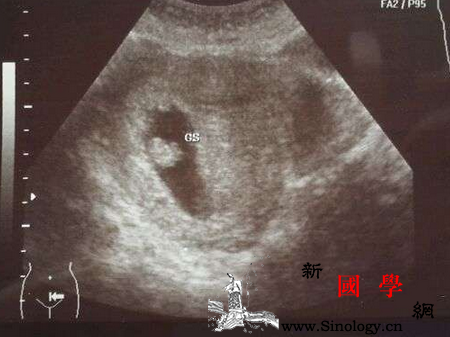

3、适时检查,一般胚胎8周左右有胎心,胎停育现象在8—12周就有可能出现,所以建议孕妇8周左右最适宜去做B超,以便及早检查胎儿和胎盘的发育情况。如果出现了胎心,大致可以放心。